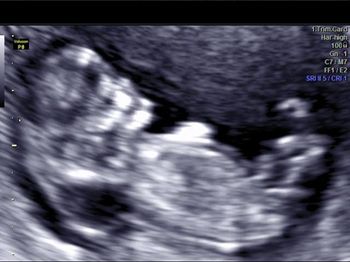

Challenge your diagnostic skills: Can you identify this anomaly?

Challenge your diagnostic skills: Can you identify this well-known anomaly?

Challenge your diagnostic skills: Can you identify this cardiac defect?